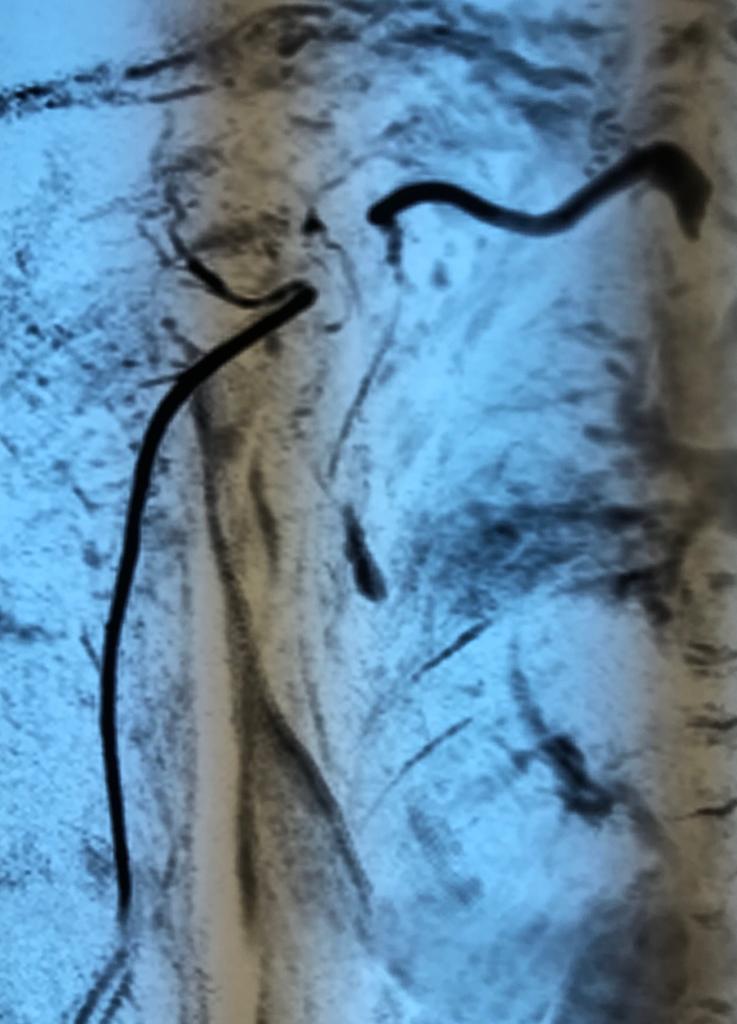

Angioresonancia periférica (miembro superior derecho).

Pacientes con luzación glehumeral anterior y fractura diafisiaria del humero, de un mes de evolución. Se complica con una oclusión de un segmento de la arteria subclavia-axilar, secundaria a trombosis.

Las lesiones de vasculares asociadas a fracturas y luxaciones del hombro son poco frecuentes, aunque potencialmente muy graves por lo que requieren un diagnóstico y actuación urgentes. Debido a la proximidad anatómica, pueden coexistir signos de compromiso de nervios mediano, radial y cubital.